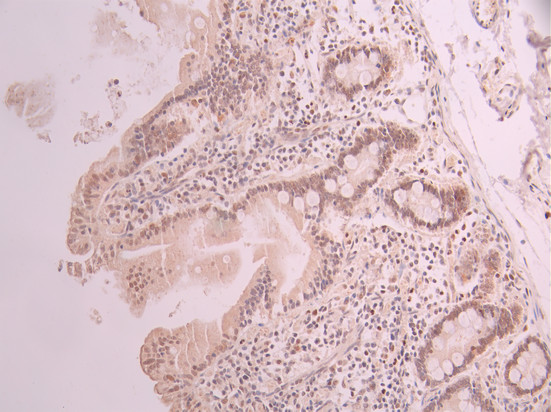

• IHC image of CSB-RA799971A0HU diluted at 1:100 and staining in paraffin-embedded human small intestine tissue performed on a Leica BondTM system. After dewaxing and hydration, antigen retrieval was mediated by high pressure in a citrate buffer (pH 6.0). Section was blocked with 10% normal goat serum 30min at RT. Then primary antibody (1% BSA) was incubated at 4°C overnight. The primary is detected by a Goat anti-rabbit polymer IgG labeled by HRP and visualized using 0.05% DAB.